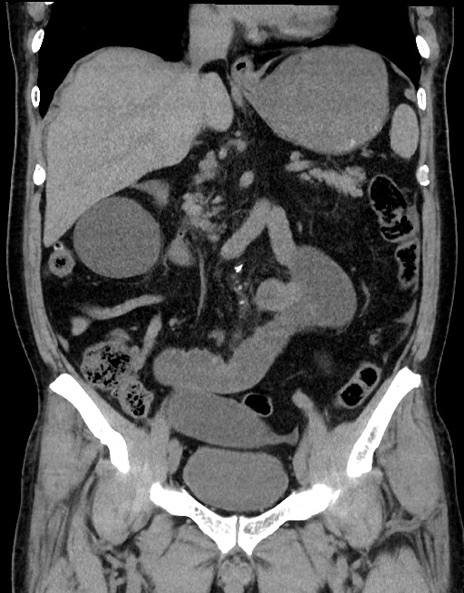

症例15(冠状断像)

【現病歴】今朝から腹痛あり。全体的に痛い。特に左上の方。排ガスが今日はない。冷や汗が出る。

【既往歴】直腸癌術後

【身体所見】左側腹部〜上腹部に圧痛あり。腹膜刺激症状明らかなではない。軽度反跳痛。左下腹部に術後瘢痕あり。